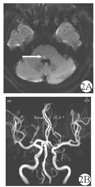

例2男,72岁,既往有高血压病史,未服用降血压药物以及监测血压。因"头晕伴恶心1 d"入院。患者1 d前无明显诱因感头晕,主要表现为感觉自身上下晃动,行走不稳,伴恶心,无呕吐。无复视,无肢体麻木无力,无言语不清及饮水呛咳。症状于活动后加重并持续存在。入院查体:心肺腹检查未见明显异常。神经系统查体:意识清楚,精神不振,言语流利。双侧眼球各方向运动充分,双眼可见水平向左持续眼球震颤,h-HIT向右侧阳性,凝视诱发眼震(gaze-evoked nystagmus,GEN)阴性;余颅神经征阴性。四肢肌力、肌张力正常。无偏身痛觉减退。双侧指鼻试验及跟膝胫试验稳准。双侧病理征阴性。行头颅磁共振示脑干梗死灶(图2)。脑梗死明确,给予口服阿司匹林肠溶片(100 mg/次,1次/d)抗血小板聚集、瑞舒伐他汀钙片(10 mg/次,1次/d)调节血脂,并给予其他对症支持治疗,病情好转后出院。

注:2A:DWI示内侧纵束高信号,提示内侧纵束梗死;2B:脑血管成像示轻度脑动脉硬化